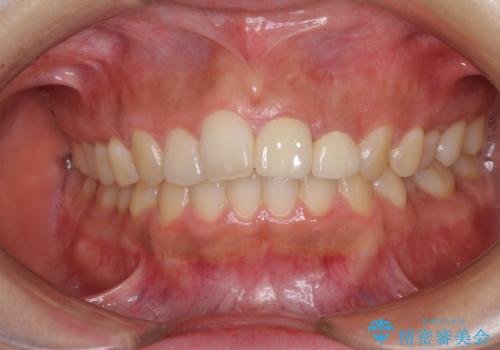

- 中学生の時にスポーツで折ってしまった前歯が変色してしまったとのことで来院された患者様です。

結婚式に向けてオールセラミッククラウンにて仕上げていくこととしました。

既にクラウンが装着されていた歯は歯根の先端に病変が認められたため、根管治療を行うこととしました。

仮歯装着の時点で自然な見た目となり、オールセラミッククラウンを装着した際には、まるで自分の歯のようと喜んでくださいました。